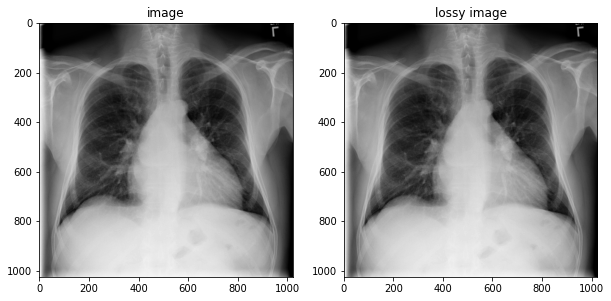

image = tfio.image.decode_dicom_image(image_bytes, dtype=tf.uint16)

lossy_image = tfio.image.decode_dicom_image(image_bytes, scale='auto', on_error='lossy', dtype=tf.uint8)

fig, axes = plt.subplots(1,2, figsize=(10,10))

axes[0].imshow(np.squeeze(image.numpy()), cmap='gray')

axes[0].set_title('image')

axes[1].imshow(np.squeeze(lossy_image.numpy()), cmap='gray')

axes[1].set_title('lossy image');